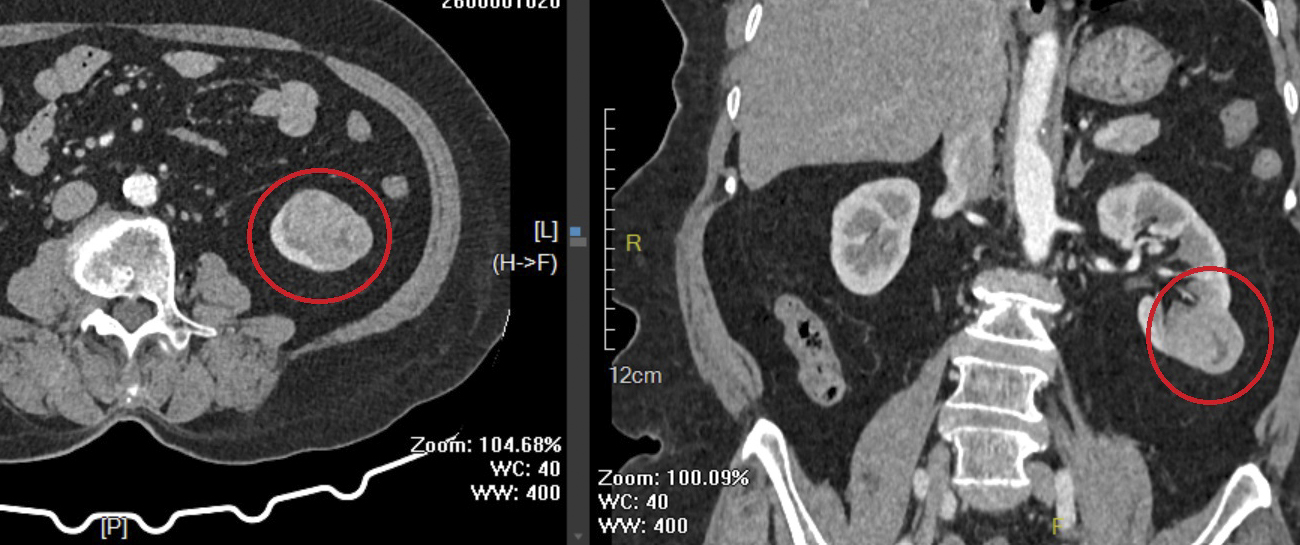

Hình ảnh khối u thận trái của người bệnh B. qua phim chụp cắt lớp vi tính.

Thời gian qua, khoa Ngoại tổng hợp, Bệnh viện Đa khoa Trung ương Quảng Nam đã tiếp nhận và điều trị nhiều trường hợp ung thư được phát hiện trong những tình huống hết sức bất ngờ. Điển hình là trường hợp người bệnh nữ P.T.B. (76 tuổi, trú xã Vạn Tường, tỉnh Quảng Ngãi) tình cờ phát hiện khối u thận trái trong quá trình nhập viện phẫu thuật viêm ruột thừa. Trước đó, người bệnh hoàn toàn không có triệu chứng lâm sàng rõ ràng hay dấu hiệu đặc hiệu liên quan đến bệnh lý ung thư.

Hình ảnh khối u có kích thước 3x4x3cm sau phẫu thuật.